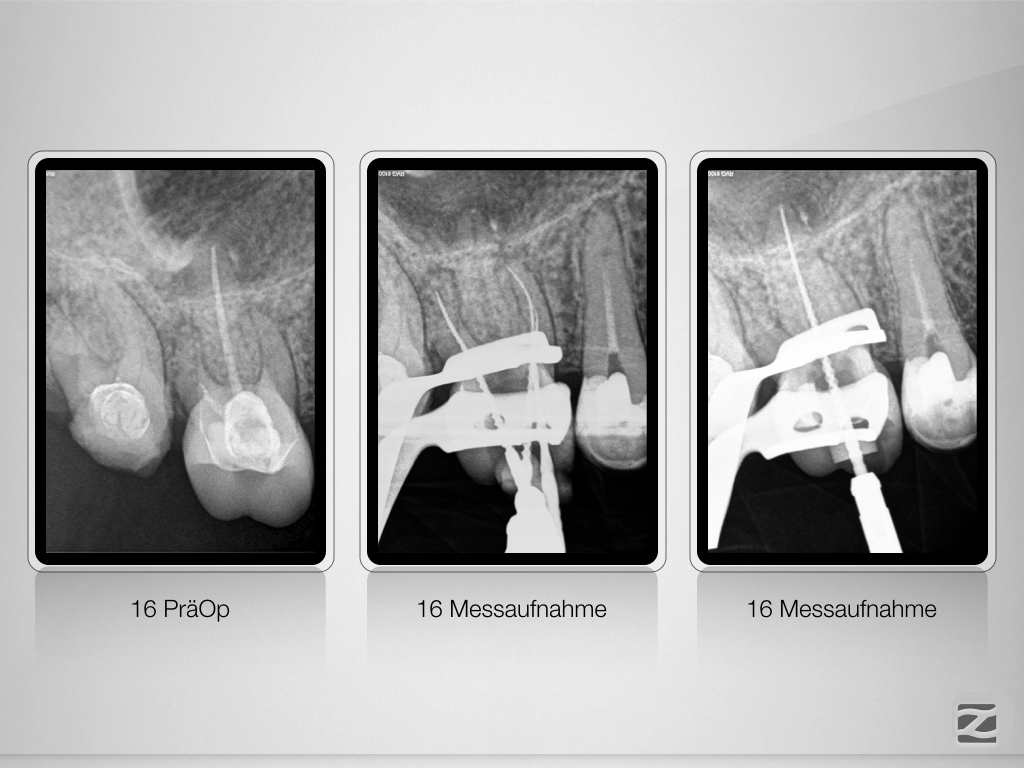

15 16 D.011

Wie hältst Du es mit dem Haarriss?